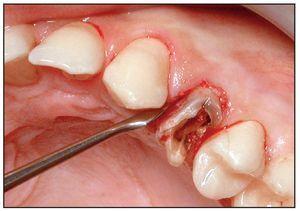

La extracción se efectuó usando las puntas del equipo de extracción (figura 1). La punta en forma de flecha se introdujo en el surco a una profundidad de 4-5 mm sin separar primero la encía del diente, alrededor de toda la circunferencia de éste. No se evidenció hemorragia mientras se progresaba en dirección apical (figuras 3a y 3b). Acto seguido, se usaron sindesmotomos rectos o angulados para cortar en profundidad las fibras del LPD (hasta 10 mm o más). Tras la sección de las fibras del ligamento, el diente se movilizó con un sindesmotomo de Claude Bernard (figura 3c) y se extrajo del alveolo con unas pinzas (figura 3d). En el caso de dientes anquilosados, se usaron sindesmotomos de vibración para desprender la raíz del hueso fijado circundante.

Figura 3 Procedimiento de extracción con las puntas vibratorias.

Figura 3c Para levantar el premolar se usó un elevador (sindesmotomo de Claude Bernard).

Figura 3d El diente se extrajo de una pieza con pinzas tras la elevación con un sindesmotomo manual.